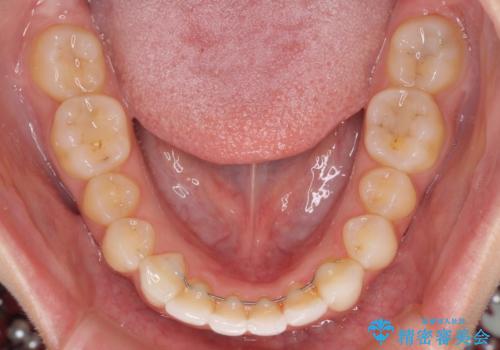

結婚式までに前歯を整えたいとのことでしたが、インビザラインでは先に奥歯を移動させてから前歯を動かすため、間に合わない可能性がありました。しかし、結婚式までに期間があったことと、マウスピースをしっかりと装着してくださったことで、十分な歯列に整えることができました。

楽しく通院していただき、辛いと思っていた治療もあっという間であったそうで、患者様には大変満足していただきました。